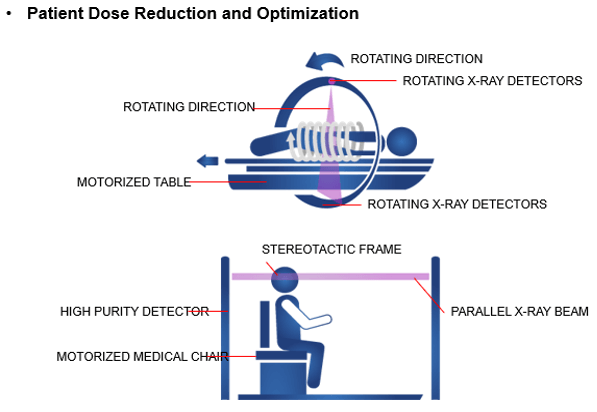

Patient Dose Reduction

The number of CT examinations in the United States has significantly increased in recent decades. The faster gantry rotation cycle times markedly reduced the need for anesthesia in children. In 2008, the Image Gently campaign was founded by the Society for Pediatric Radiology, the American Society of Radiologic Technologists, the American College of Radiology, and the American Association of Physicists in Medicine (AAPM) with the goal of increasing pediatric CT radiation dose awareness by starting a national education and awareness program.

Pediatric dose reduction is important for the safety of children. There are many practices recommended by the Alliance for Radiation Safety in Pediatric Imaging that reduce the dose to children. Such things as scanning only when necessary, reducing the radiation used, asking your medical physicists to monitor your CT techniques and not using multiphase scanning are all important components of pediatric scanning.

Adult Dose Reduction

In 2009, the American College of Radiology (ACR) and the Radiological Society of North America (RSNA) established the Joint Task Force on Adult Radiation Protection to address the safe and effective use of medical imaging and to incorporate dose optimization into all imaging practices Using dose optimization in scanning adults and geriatric patients is the radiation protection principle used to make sure that patient doses are kept as low as reasonably achievable (ALARA). It refers to reducing the radiation dose while keeping the image quality needed to obtain a quality image. Geriatric patients who are very small may need to have pediatric techniques utilized.

Radiation exposure to the patient has become a concern for the radiologist in the multidetector computed tomography (CT) era. With the introduction of faster multidetector CT scanners, various techniques have been developed to reduce the radiation dose to the patient; one method is automatic exposure control (AEC).

Let’s look at the various dose modulation techniques that are available that help reduces patient dose. CARE Dose 4D (Siemens) assesses the size of the patient cross-section being scanned and adjusts tube current relative to the reference effective milliamperage. It aims to provide adequate image noise, which varies depending on the size of the patient. This system operates on the principle that different-sized patients require different levels of noise to maintain adequate image quality.